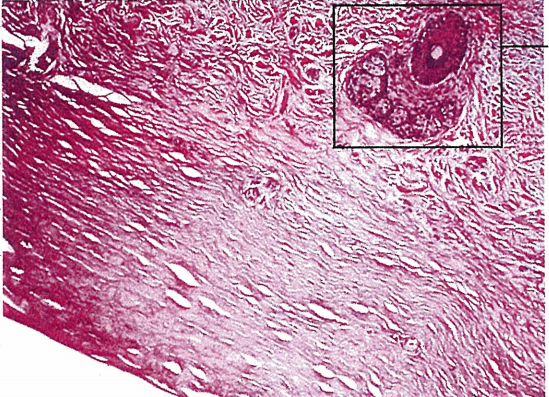

조직소견으로는 문자그대로 피부와 유사한 종양이기에,

진짜 피부 즉, 진피로 이루어져 있어,

진피의 구성조직과 피부 부속기관이 자리하고 있씁니다.

단단한 섬유 조직과 모공, 피지샘 등의 진피 구조들이 결막상피에 덮여 있습니다.